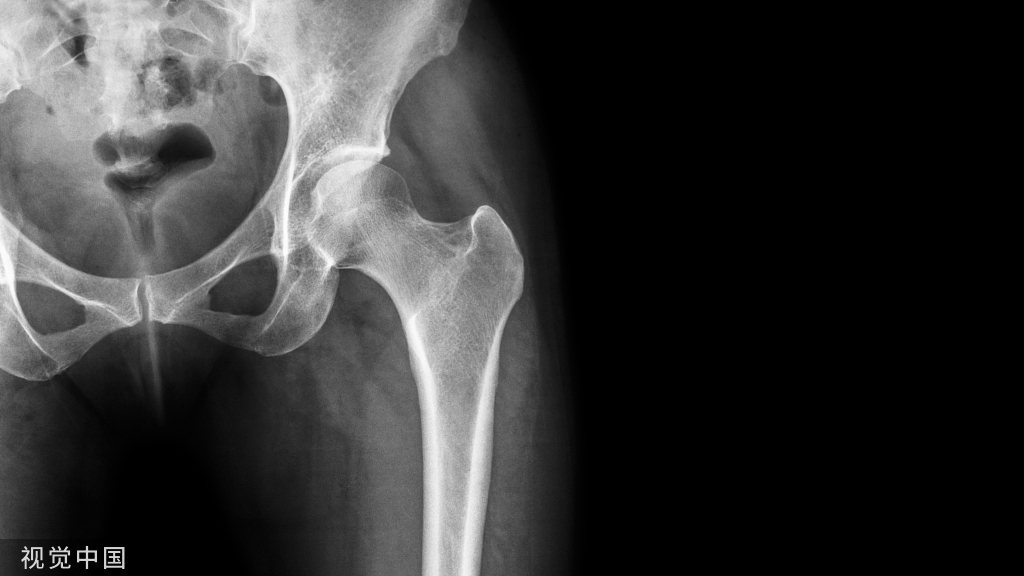

影像学表现

X线片表现

正位片:不易显示峡部病变。椎板外测端呈断肩样改变;椎板外侧上下缘显示边缘硬化的新月状凹陷;椎弓根区密度不均,结构紊乱或有破碎;或见椎体旋转。

侧位片:椎弓根后下方细长或见透明裂隙,关节突间常见硬化征象;上位病变椎体出现滑移;椎间隙狭窄,椎间隙前后比例异常;可对滑脱程度进行具体测量。